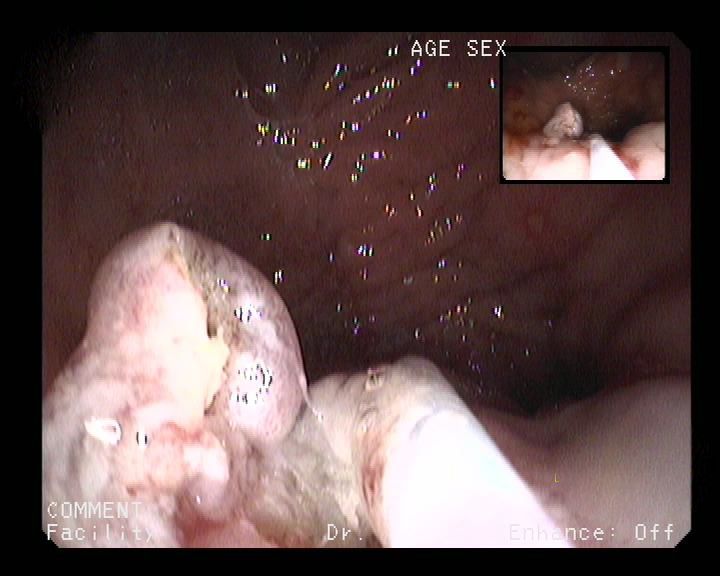

Paciente mujer de 72 años de edad con antecedentes de cardiopatía isquémica (IAM anteroseptal),TEP leve (tratamiento con acenocumarol) y trastorno depresivo. Consulta en enero del presente año por clínica dispéptica inespecífica sin síntomas de alarma. Anlíticamente no se encontraron alteraciones de interés. Se realizó una gastroscopia que observó cierta dificultad en la distensión de la cámara gástrica a la insuflación con biopsias de cuerpo y antro gástrico para determinación de H. Pylori (ureasa rápida), que resultó positivo. Se hizo tratamiento erradicador para H. Pylori (pauta con amoxicilina y claritromicina durante 7 días) que resultó eficaz. En el TAC abdominal se apreciaba engrosamiento parietal circunferencial de la porción distal del antro y píloro con mala definición de la transición con el tejido graso adyacente en el borde mesentérico que no permitía descartar afectación mas allá de la serosa. Ante estos hallazgos se realizó una USE radial: se observa en zona de transición de cuerpo-antro sobre todo hacia curvadura mayor, unos pliegues engrosados con poca distensibilidad a la insuflación y friable al roce con erosiones fibrinadas. Estenosa levemente la luz. Se observa un engrosamiento de la segunda y tercera capa que rompe en algunas zonas primera capa. La cuarta capa y serosa parecen respetadas. No se observa infiltración de parénquima hepatico ni cuerpo-cola pancreática. Sugiere proceso neoformativo (linfoma?). Por este motivo se solicitó una macrobiopsia gástrica que resultó inconcluyente (metaplasia enteroide).

En el seguimiento, a los 8 meses del inicio del cuadro, la paciente presenta una acentuación de los síntomas dispépticos con pérdida de peso y distensión abdominal que corroboŕó la existencia de ascitis en moderada cuantía. En este momento en la analítica practicada destaca un aumento marcado del Ca 19.9 (447,6 UI/ml) y CEA-125 (434,2 UI/ml). EL TAC de control muestra unos hallazgos similares al primero, pero con líquido libre subhepático, periesplénico, en ambas gotieras paracólicas, sobre todo izquierda, y en pelvis. Se realiza nueva macrobiopsia que ya confirma la existencia de una adenocarcinoma con células en anillo de sello.